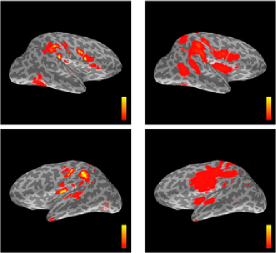

Refer to caption

Figure 5: Simulation 2. Comparison of the maps produced by the Static model particle filter (first column), the Random-Walk model particle filter (second column), dSPM (third column), RAP-MUSIC (fourth column) and L1L2subscript𝐿1subscript𝐿2L_{1}L_{2} (fifth column) at different time points: 30 ms (first row), 50 ms (second row), 75 ms (third and fourth rows), 90 ms (fifth and sixth rows). Black circles mark the locations of the true sources.